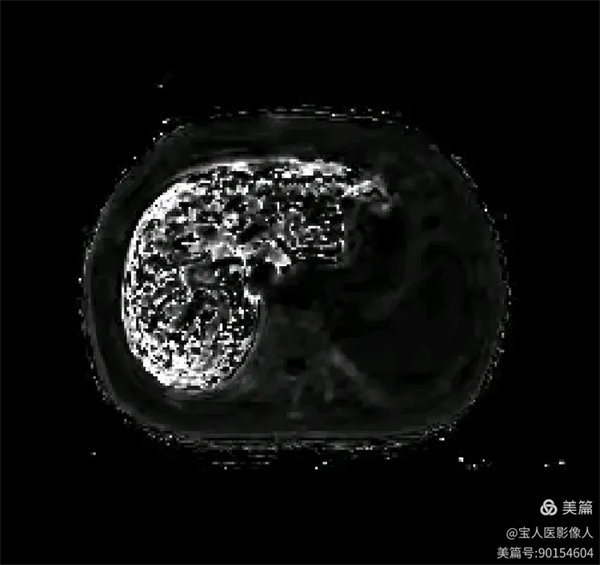

R2*圖,肝實質信號不均勻明顯升高。

R2*圖,測量全肝不同部位肝實質的R2*值都明顯升高。